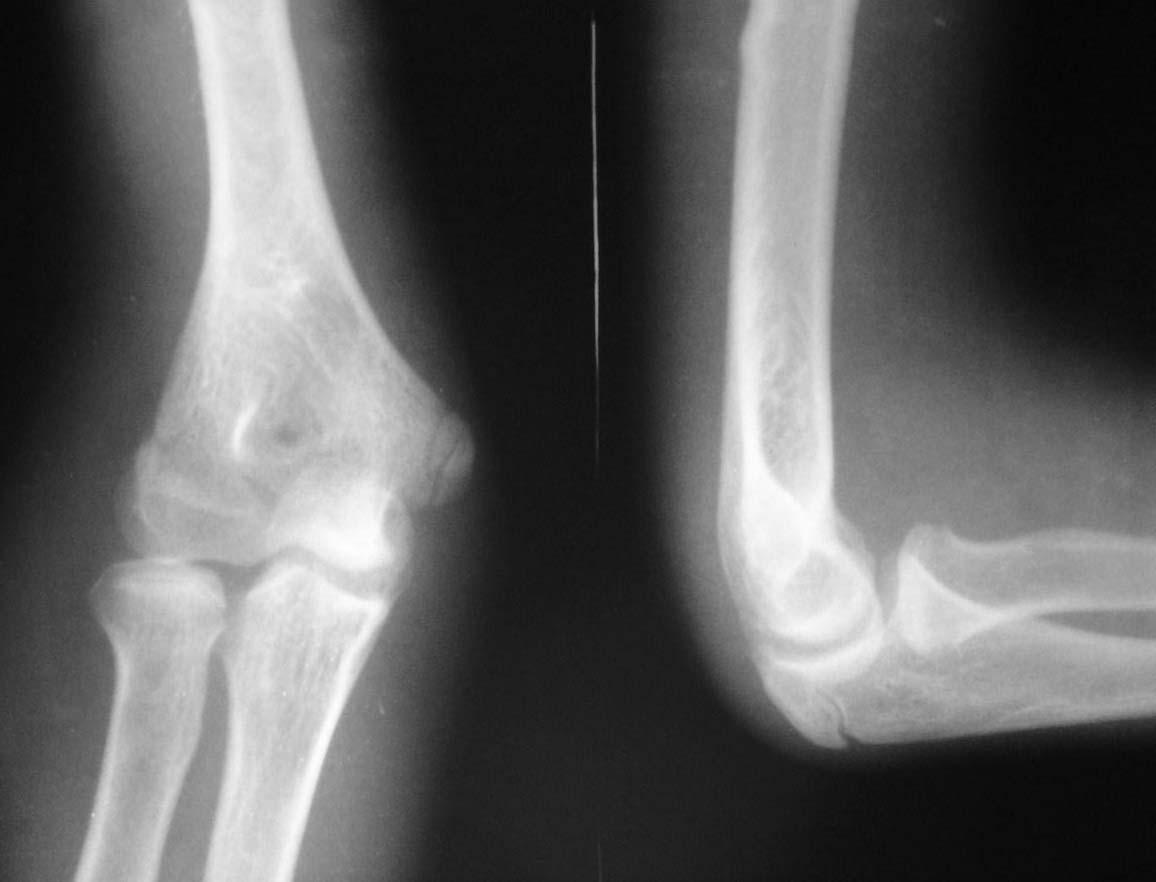

治疗当天,秦女士就感觉四肢关节疼痛明显减轻,关节肿胀现象也有些削减的趋势。于是她对这个治疗充满信心,也对马友文主任充满信任。三个疗程治疗结束后,秦女士一脸的兴奋,她说自己的风湿症状消失了,疼痛红肿现象有效不见,也没有头晕目眩、恶心呕吐,关节活动自如。马友文主任检查后发现,行动关节正常,未见异常,受损关节组织得到恢复,血压等检查均正常。

(图:患者治疗后肘关节X线片示)